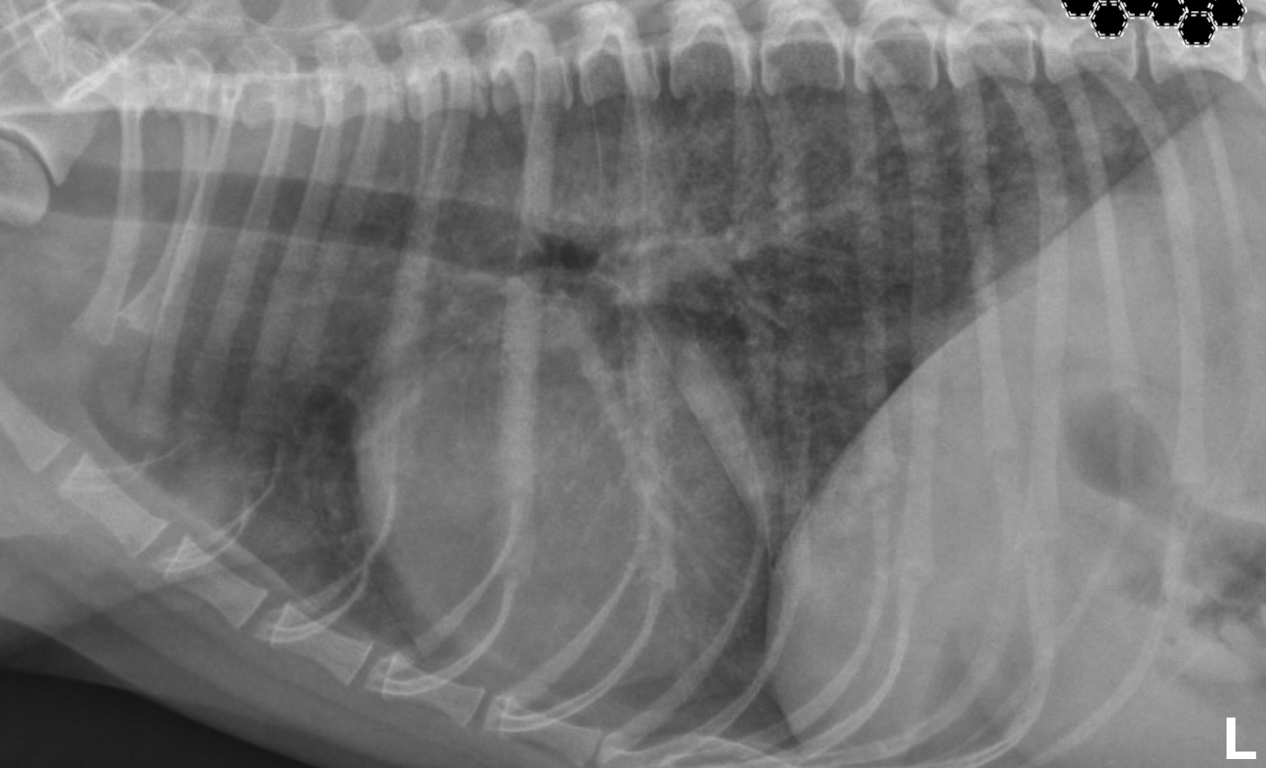

signs of pneumothorax on xray

lung lobe margin retraction radiolucent pleual space with no pulmonary vessels cardiac silhouette seperated from sternum by gas

pneumothorax Lung lobe margin retraction Radiolucent pleural space – Devoid of pulmonary vessels

**pneumothorax** Lung lobe margin retraction Radiolucent pleural space – Devoid of pulmonary vessels **Cardiac silhouette separated from sternum by air**